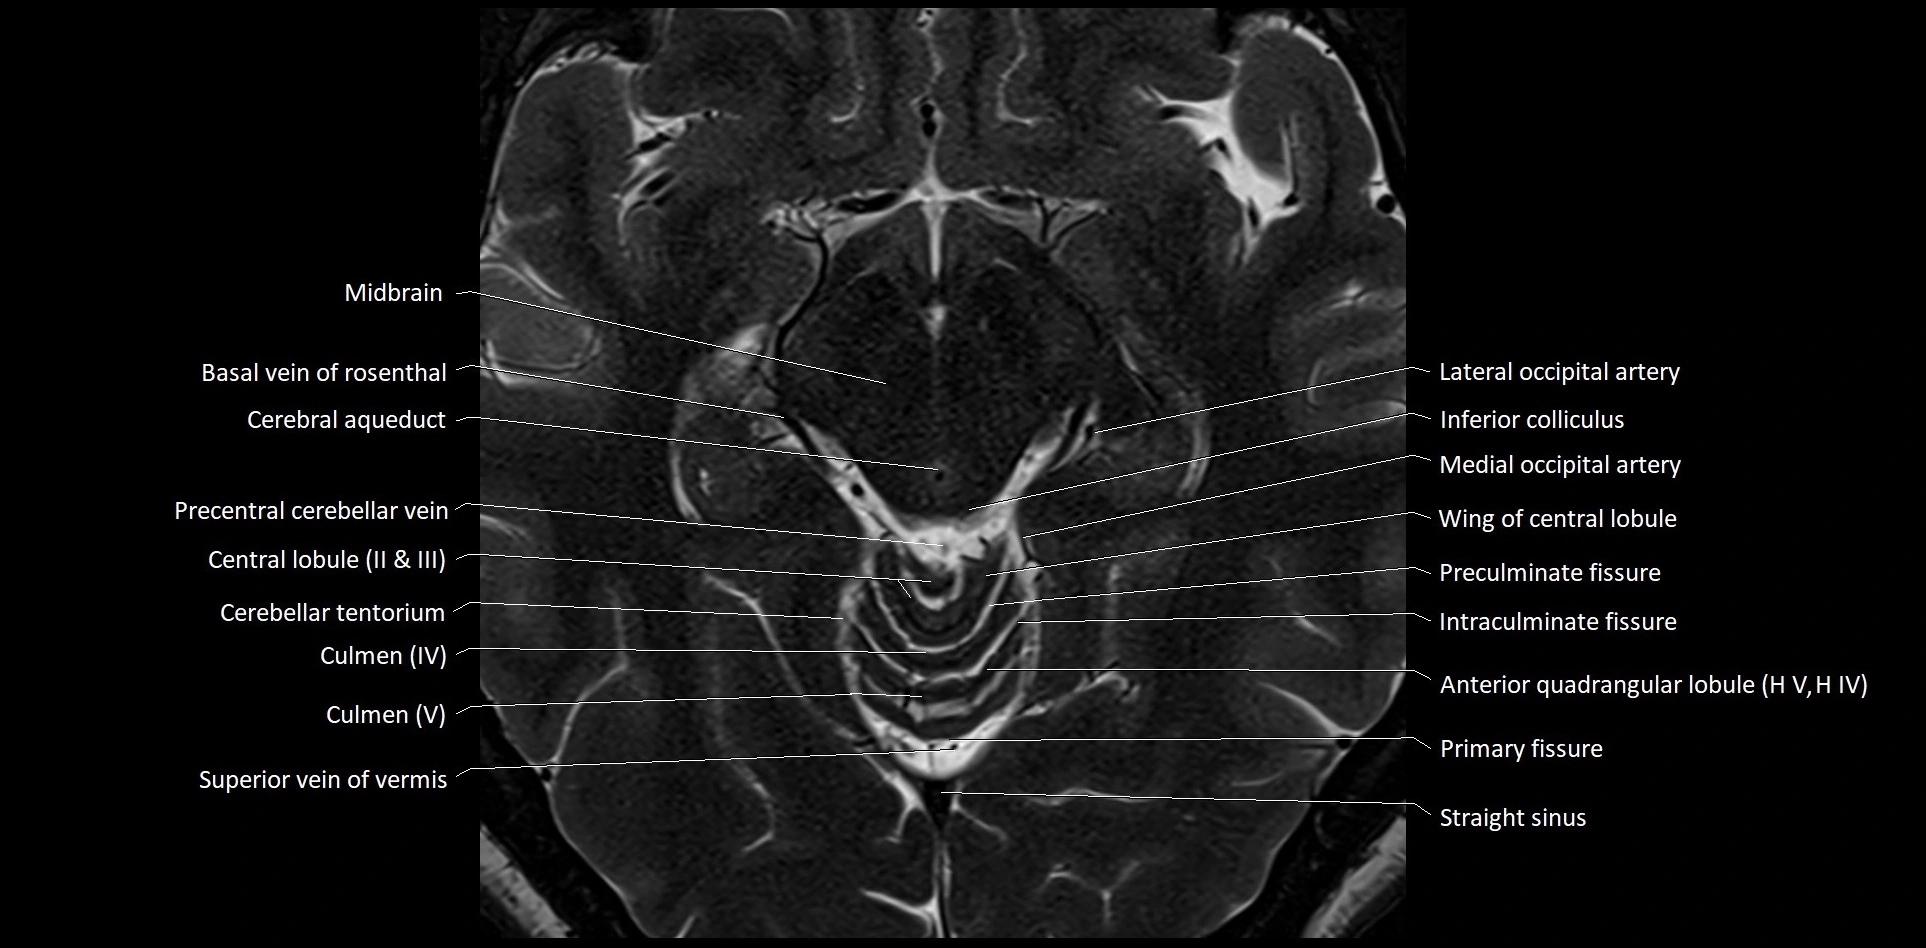

MRI images